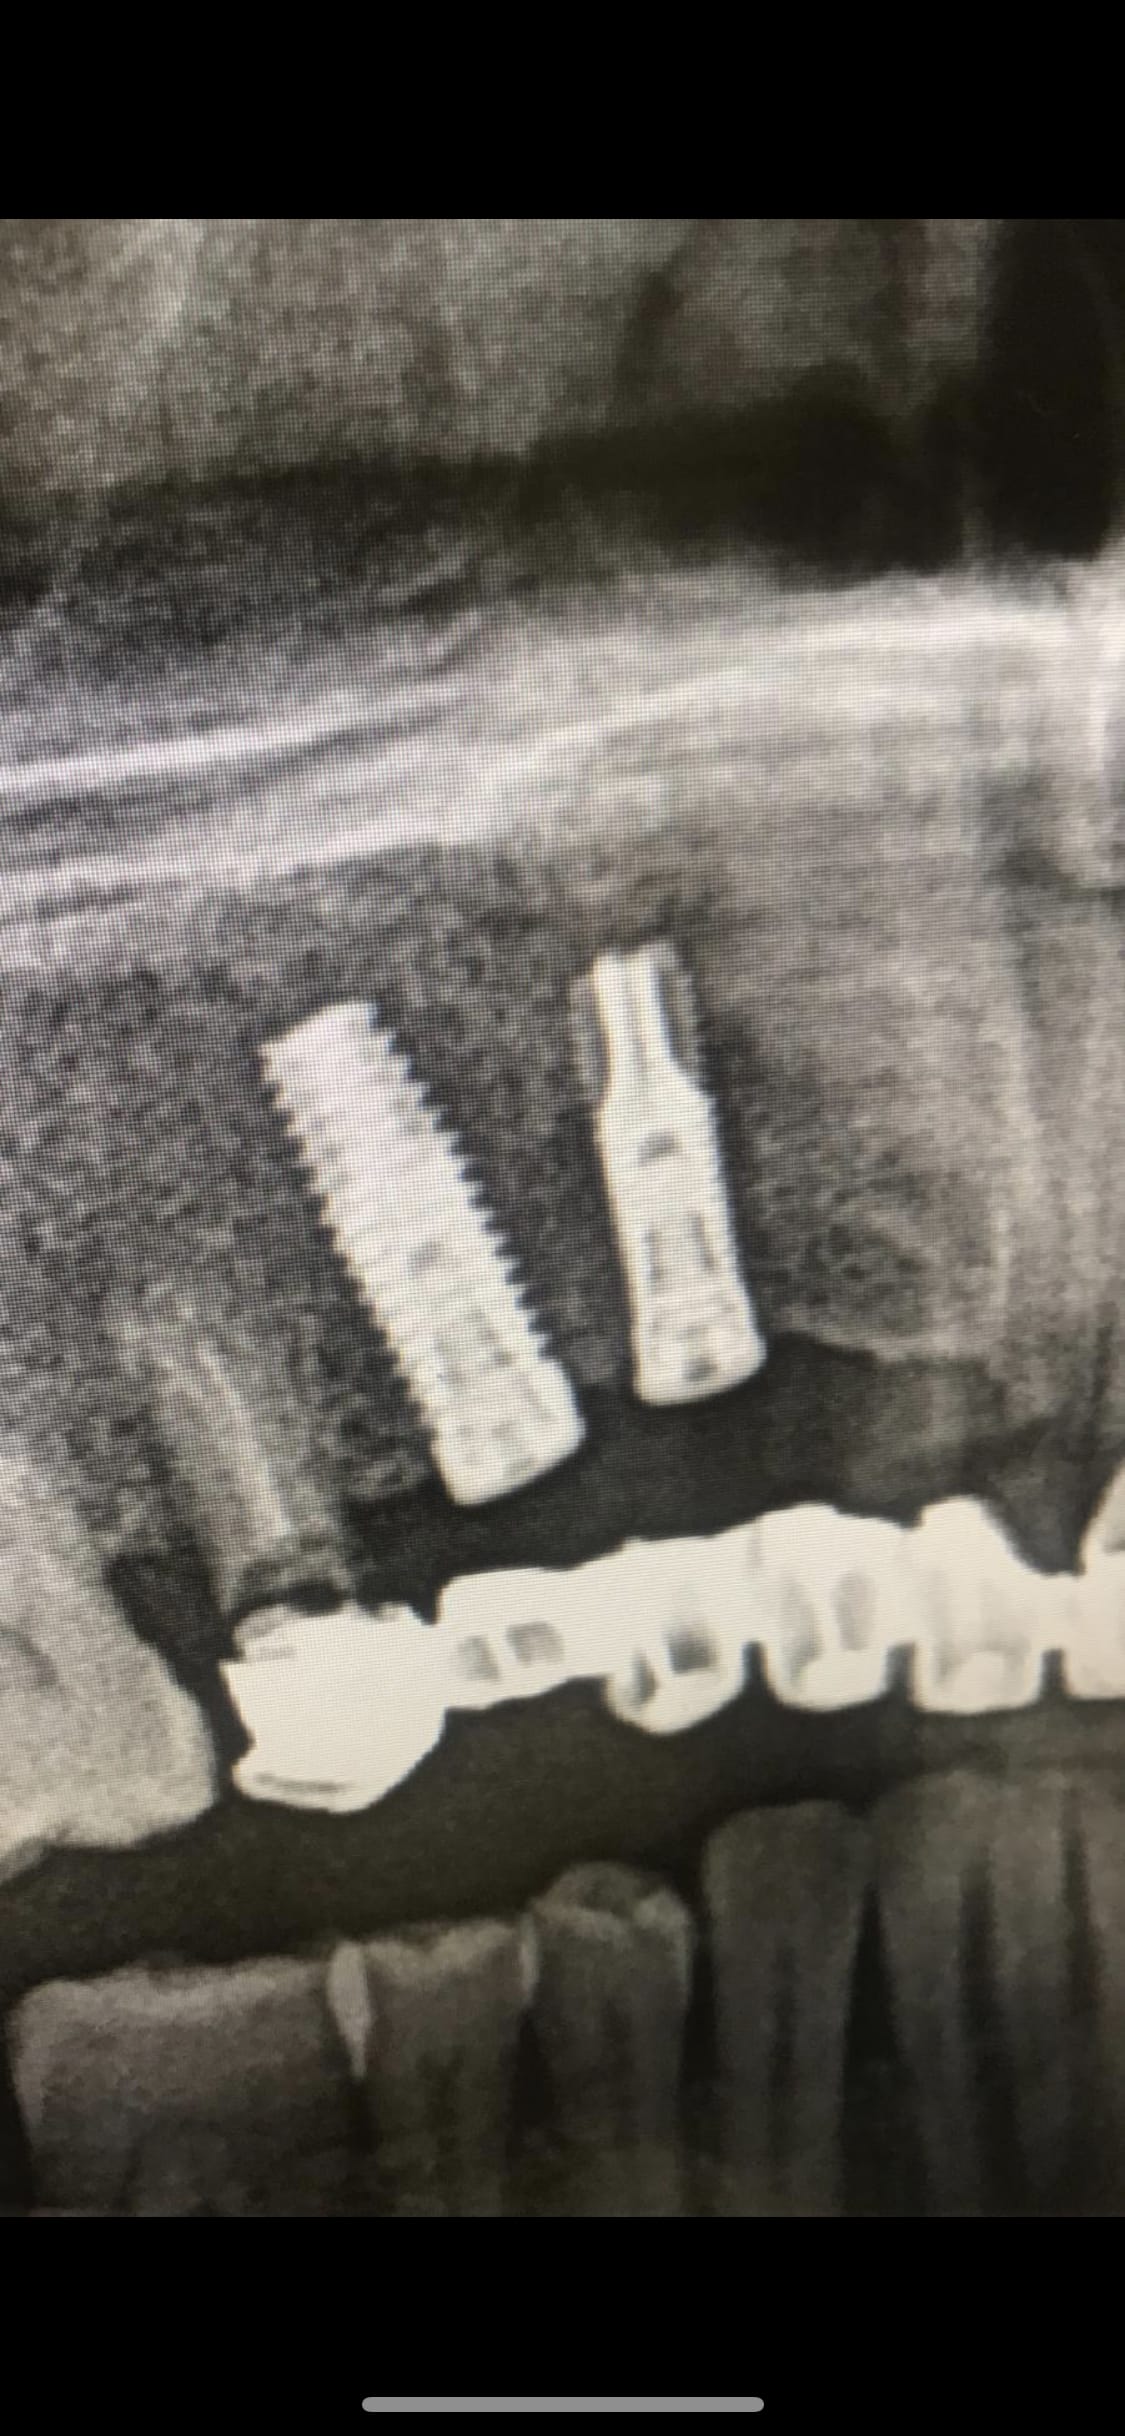

Quelqu’un pourrait il m’indiquer quels sont les implants présents ici?

Rétro stp!!!! histoire d'être sûr à 100%....

maintenant, une connexion conique dans un implant cylindrique comme çà....je veux bien mettre un billet sur un Medical Production....

http://www.medical-production.eu/fr/component/tags/tag/i-cone.html

Merci Pluton ! Voici la retro !